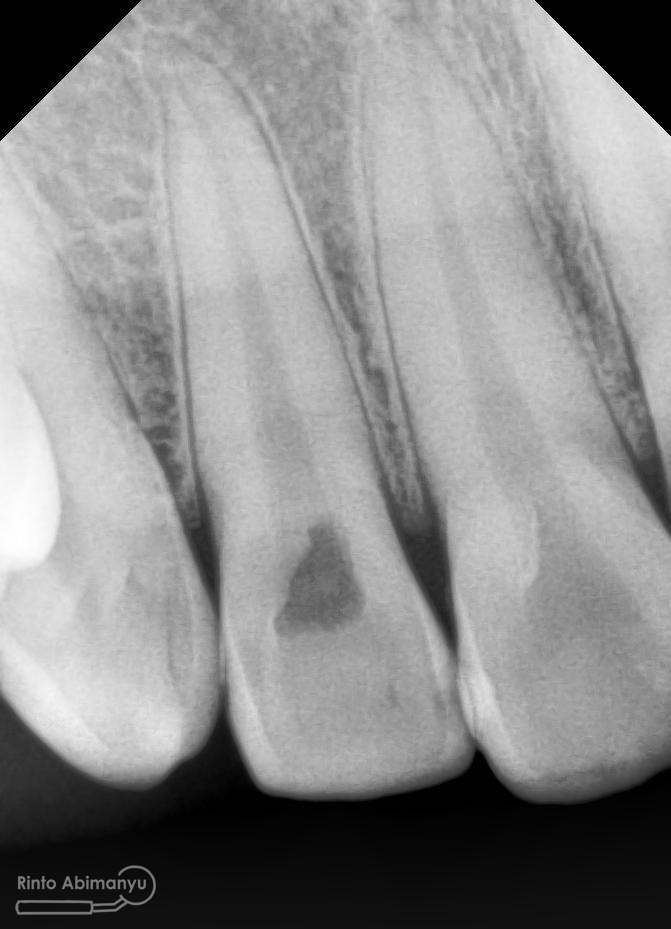

dan ini foto ronsen nya…

Foto radiografis gigi 11 21 22 yang mengalami fraktur

Dari pemeriksaan radiografis lokasi fraktur menyerempet kamar pulpa pada ketiga gigi tersebut… Saya sampaikan kepada pasien bahwa ketiga gigi tersebut memerlukan perawatan saluran akar terlebih dahulu baru kemudian dilanjutkan dengan restorasi indirek… kenapa saya pilih restorasi indirek? Pertimbangannya adalah sisa struktur mahkota gigi yang ada bila hanya di “sambung” dengan restorasi direk dalam jangka panjang rentan mengalami kerusakan, yang kedua pemilihan warna akan lebih maksimal pada kasus ini…. Pasien setuju dengan rencan perawatan yang saya jelaskan…